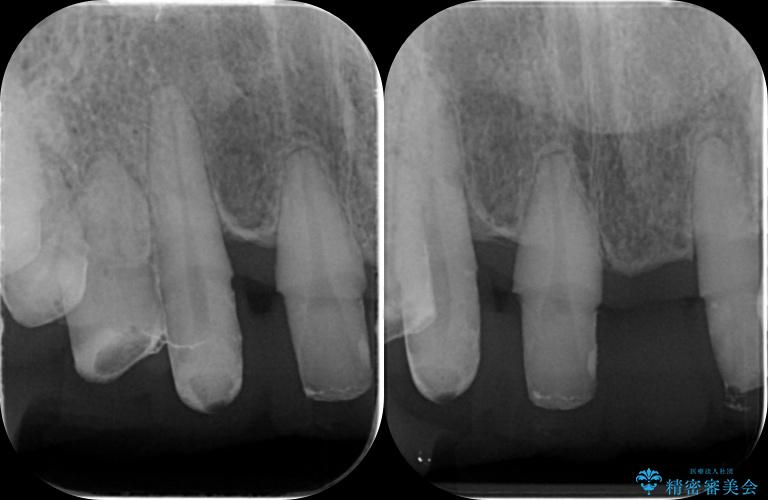

治療前

歯の総合的なマネージメントを行う包括的歯科治療の実践[ 歯周病・矯正・セラミック補綴 ] 治療前画像 歯の総合的なマネージメントを行う包括的歯科治療の実践[ 歯周病・矯正・セラミック補綴 ] 治療前画像 歯の総合的なマネージメントを行う包括的歯科治療の実践[ 歯周病・矯正・セラミック補綴 ] 治療前画像 歯の総合的なマネージメントを行う包括的歯科治療の実践[ 歯周病・矯正・セラミック補綴 ] 治療前画像 歯の総合的なマネージメントを行う包括的歯科治療の実践[ 歯周病・矯正・セラミック補綴 ] 治療前画像 歯の総合的なマネージメントを行う包括的歯科治療の実践[ 歯周病・矯正・セラミック補綴 ] 治療前画像 歯の総合的なマネージメントを行う包括的歯科治療の実践[ 歯周病・矯正・セラミック補綴 ] 治療前画像